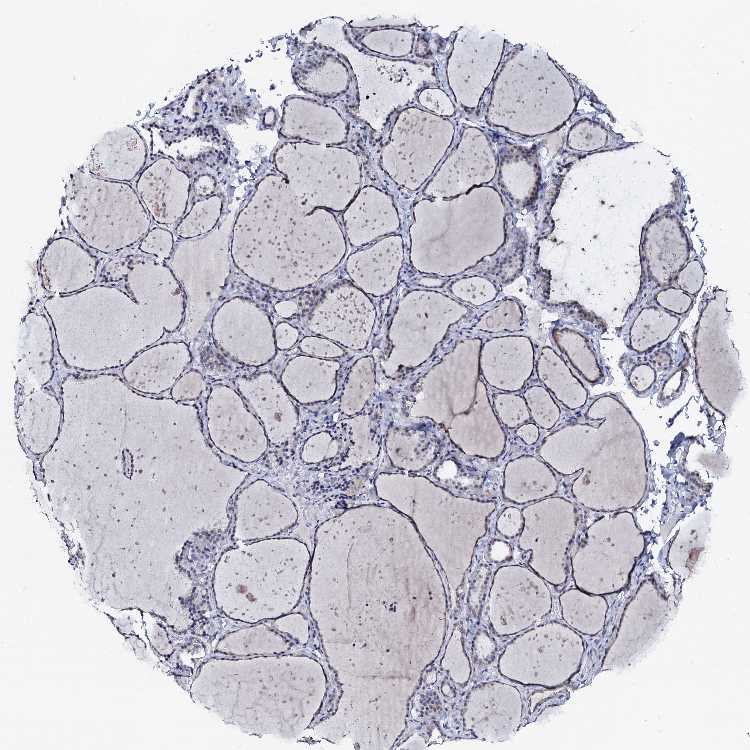

THYROID GLAND - Antibody stainingi

Antibody staining in the annotated cell types in the current human tissue is reported as not detected, low, medium, or high, based on conventional immunohistochemistry profiling in selected tissues. This score is based on the combination of the staining intensity and fraction of stained cells.

Each image is clickable and will lead to virtual microscopy that enables deeper exploration of all samples and also displays staining intensity scores, fraction scores and subcellular localization as well as patient and tissue information for each sample.

Antibody HPA039360

Glandular cells Low